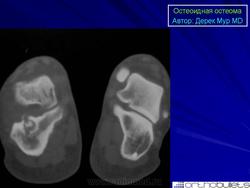

Рентгенограмма и КТ-изображение типичной остеоид остеомы в проксимальном отделе большеберцовой кости.

Внутрикорковая остеоид остеома проксимального метафиза большеберцовой кости у 14-летней девочки.

КТ изображение фиксирует периостальную реакцию, утолщение кортикльного слоя, очаг (стрелка) с центральной минерализацией. Имеет место реактивный склероз костного мозга (*), прилегающего к очагу.

МР изображение. «Периостальная реакция» (наконечники стрел).